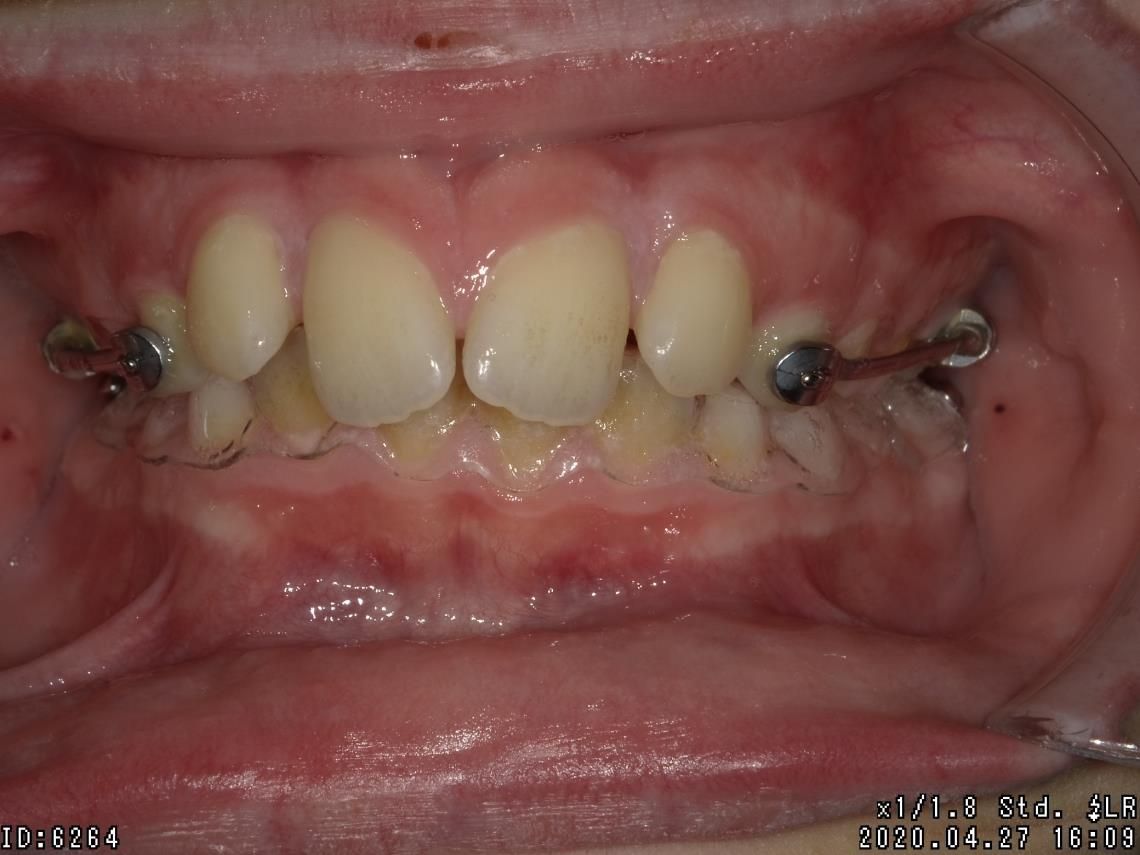

LES BAGUES

Cet appareil dentaire fixe est composé de brackets ou bagues, sortes de petits boutons en métal, en plastique ou en céramique, collés sur les dents et reliés par un fil. Il permet de déplacer les dents du patient dans la direction optimale, de les réaligner au fur et à mesure, de traiter des cas complexes de manque de place et des dents retenues ou dystopiques. Le traitement est moins tributaire de la coopération du patient.